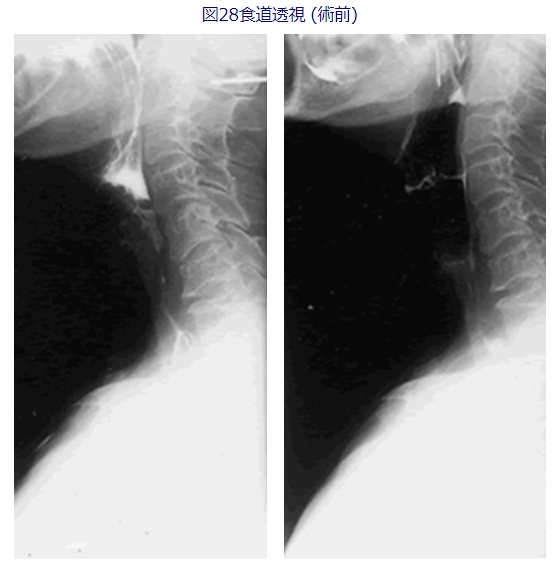

私が幾つかの施設で経験した10例ほどの症例では、頭頸部腫瘍術後の嚥下障害では余り有効ではありませんでしたが、コミュニケーションのとれる脳血管障害には食道入口部の拡張手術がある程度有効でした。図28、29に一例の術前術後の嚥下バリウム像を呈示します。